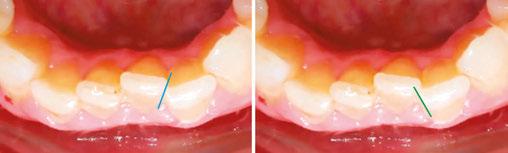

Angel Aligner with integrated angelButtons have transformed my approach to demanding cases. The angelButtons can be positioned on four to eight points on any tooth (Figure 1). With traditional hooks and bonded buttons, multidirectional movement is limited, and force is concentrated on the specific tooth to which the elastic is engaged.

Figure 1: The integrated angelButton of Angel Aligner can be positioned on four to eight points on any tooth for 360° traction

Maintain CL I occlusion. Develop the transverse relationships, eliminate the posterior negative root torques, and resolve the excessive gingival display via full-arch nonsurgical impaction. All vertical changes would be accomplished using only Angel Aligner, TADs, and elastics. Her maxillary lateral incisors may later require buildups to improve the Golden Proportion of the anterior teeth. My iOrtho software setup for maxillary intrusion was to place angelButtons (blue) between the U2s-3s, U4s-5s, and distal of the U6s (Figure 4).